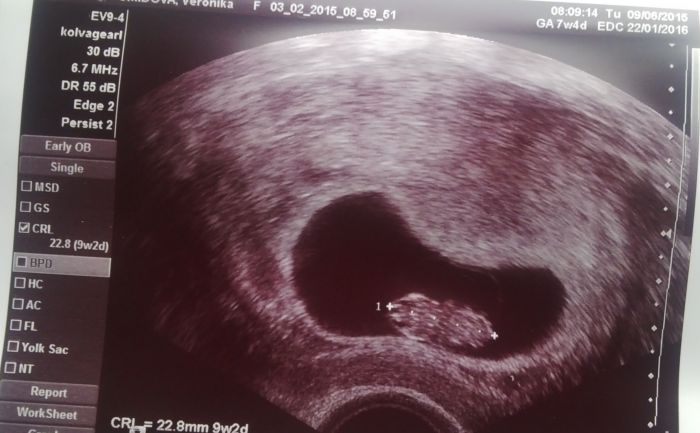

Ahoj holky :) Tak já mám kontrolu za sebou a spadl mi obrovský kámen ze srdce :) Včera mi bylo celý den špatně, břicho mi bolelo jako ještě nikdy,chvilema jsem měla až křeče, tak jsem vážně měla strach. Naštěstí je vše v pořádku, brouček za tech 14 dní krásně vyrostl Z 8,9 mm na 22,8 mm tak jsem moc šťastná :) srdíčko má jako zvon ;) Prý jsme o 14 dní starší, příští čtvrtek si jdu pro průkazku,na další ultrazvuk a že už by se mělo přesněji určit jak "staří " vlastně jsme :) Se mi z té gynďasovo kozy ani nechtělo slézt. Bych tam klidně ležela dál a pozorovala a poslouchala mrně :-D